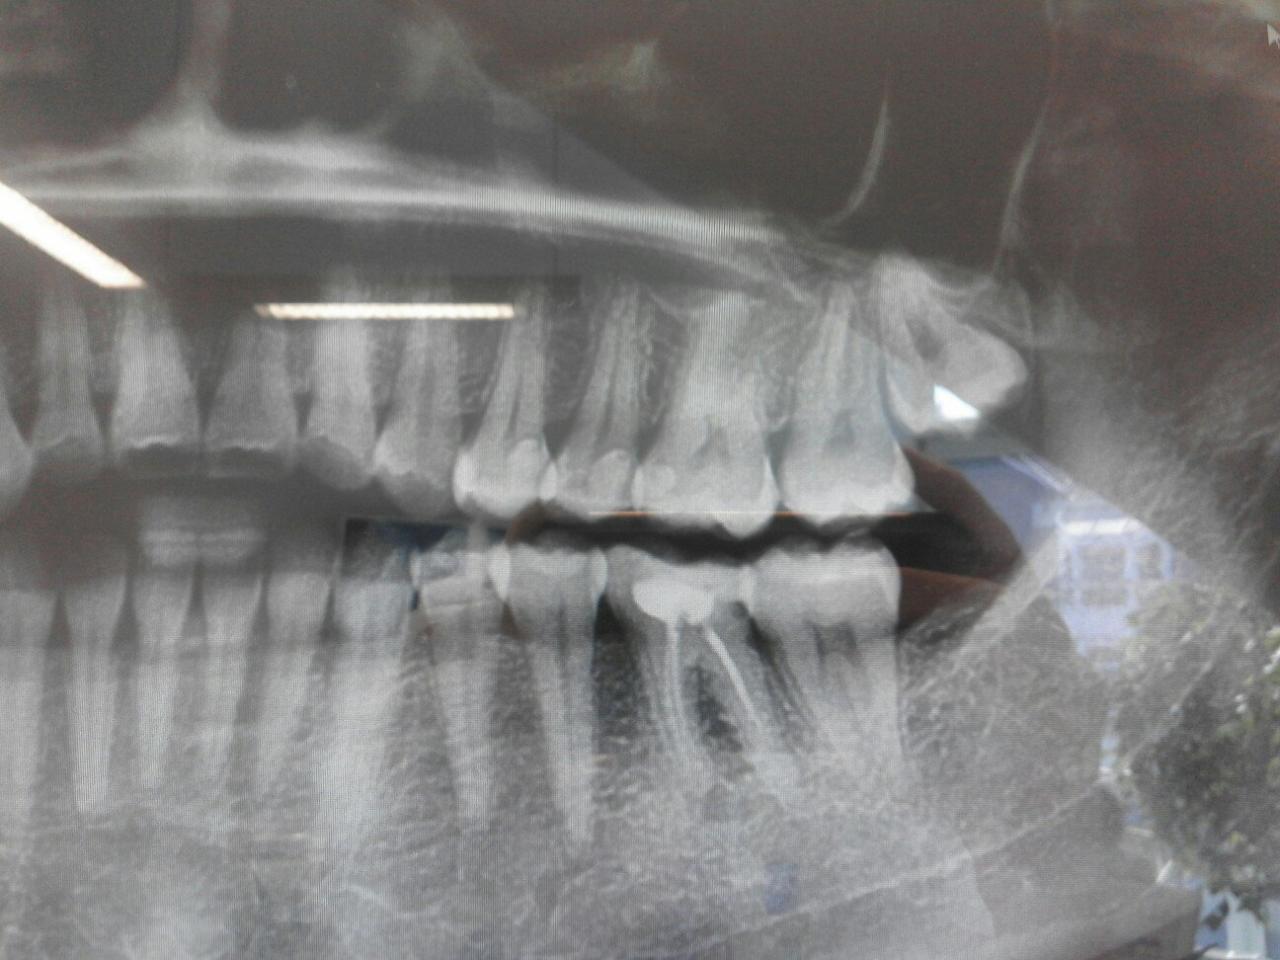

Вот на панорамном снимке хорошо видно.